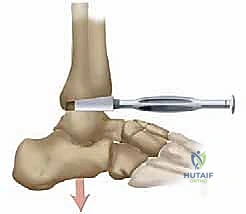

* يتم تصميم المكون الظنبوبي (Tibial Component) ليُزرع عمودياً على المحور الطولي الأمامي للظنبوب مع ميلان خلفي بمقدار 10 درجات، مما يحافظ على التوزيع الطبيعي للقوى.

* أما المكون الكاحلي (Talar Component)، فيتم وضعه بشكل موازٍ للأرض أو للجانب السفلي من القدم الحاملة للوزن.

* بينهما، توضع حشوة من البولي إيثيلين عالي الكثافة (UHMWPE) التي تعمل كغضروف صناعي، مما يضمن حركة طبيعية، متوازنة، وخالية من الألم.